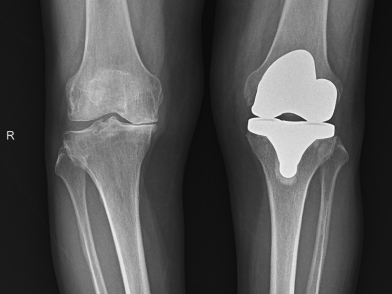

Η ολική αρθροπλαστική γόνατος είναι μια από τις πιο επιτυχημένες και συχνές ορθοπαιδικές επεμβάσεις παγκοσμίως. Με απλά λόγια, πρόκειται για την αντικατάσταση των φθαρμένων επιφανειών της άρθρωσης του γόνατος (λόγω αρθρίτιδας ή τραυματισμού) με ειδικά τεχνητά εμφυτεύματα, τα οποία ονομάζονται προθέσεις.

Σκοπός της επέμβασης δεν είναι μόνο η εξάλειψη του πόνου, αλλά και η ταυτόχρονη διόρθωση της παραμόρφωσης του γόνατος (όπως το γόνατο που “γέρνει” προς τα μέσα ή προς τα έξω), επιτρέποντας στον ασθενή να ανακτήσει την πλήρη λειτουργικότητα και κινητικότητά του. Τα εμφυτεύματα που χρησιμοποιούνται είναι κατασκευασμένα από κράματα μετάλλων (όπως τιτάνιο ή κοβάλτιο-χρώμιο) και ειδικά πολυμερή (πολυαιθυλένιο), τα οποία είναι απολύτως βιοσυμβατά με το ανθρώπινο σώμα, εξασφαλίζοντας μακροζωία και αντοχή.

Πριν την αρθροπλαστική, θα υποβληθείτε σε έναν πλήρη προεγχειρητικό έλεγχο. Αυτός περιλαμβάνει αιματολογικές εξετάσεις, καρδιολογικό έλεγχο (ΗΚΓ, υπέρηχος καρδιάς αν απαιτείται), ακτινογραφία θώρακος και εξειδικευμένες ακτινογραφίες του γόνατος (και συχνά ολόκληρου του ποδιού) για την ψηφιακή προσομοίωση και τον ακριβή υπολογισμό των διαστάσεων των εμφυτευμάτων.